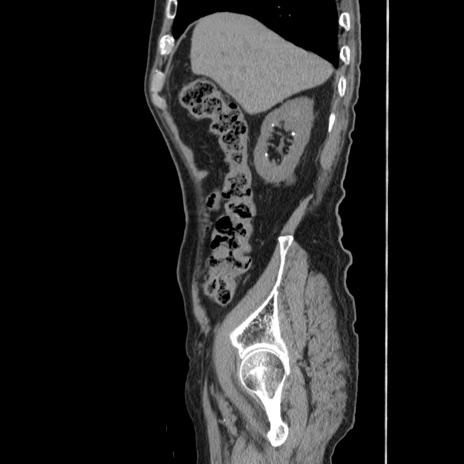

冠状断像